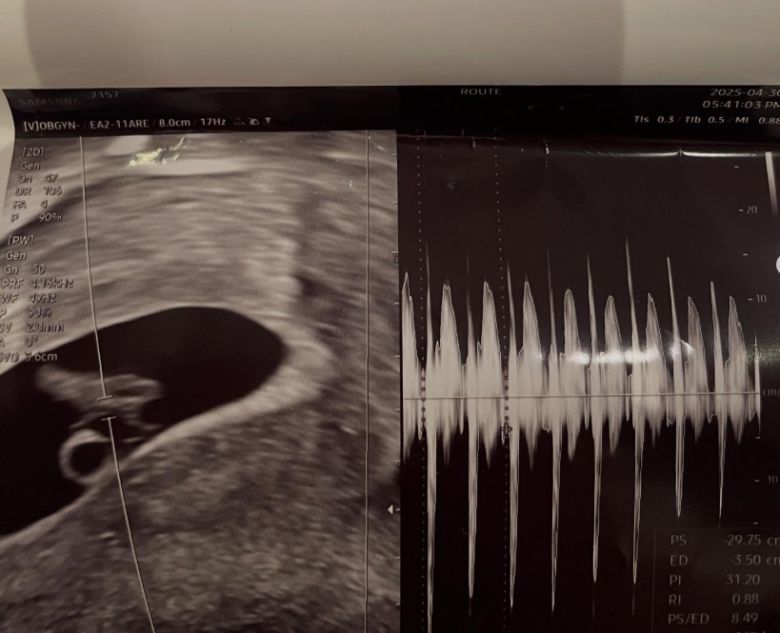

그러던 중 서민재는 지난달 중순 임신 사실을 확인했고 곧바로 남자친구 A씨에게 해당 사실을 알렸다고 전했다. A씨는 서민재의 결정을 존중하겠다며 고민할 시간을 줬고 서민재는 숙고 끝에 출산을 결심했다고 한다. 양측 부모에게도 이를 알리고 결혼과 출산에 대해 논의하기로 했다. 하지만 서민재는 A씨의 부모로부터 "아이를 낳으면 아들과 인연을 끊겠다"는 말을 들었다고 주장했다. 이에 대해 그는 "사실상 낙태를 요구하는 것 아니냐"고 반발했다.